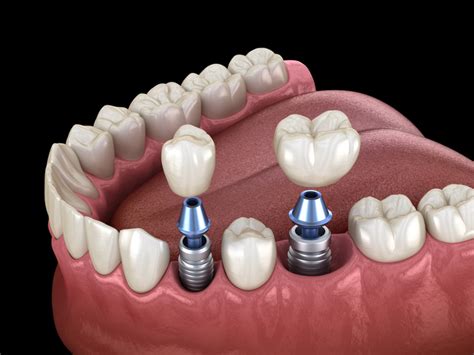

Implante endoóseo: el que más se usa (y con razón)

Este es el implante dental de referencia. El de toda la vida. El que más se coloca en las clínicas y el que, si tienes buena base ósea, te van a recomendar casi siempre. ¿Por qué? Porque se integra con el hueso de la mandíbula como si fuera la raíz natural del diente perdido.

¿Cómo funciona? El dentista coloca un tornillo de titanio dentro del hueso. Después de unas semanas o meses -depende del caso- ese tornillo se “pega” al hueso, lo que se llama osteointegración. Una vez que está bien sujeto, se coloca la corona (la parte visible del diente).

¿Cuándo es buena idea? Cuando tienes hueso suficiente. Si buscas una solución duradera y estética. Si quieres un resultado que parezca tu diente de toda la vida.

Ventajas:

- Tiene un aspecto natural.

- No se mueve ni te da problemas al comer.

- Ayuda a conservar el hueso de la mandíbula, que tiende a perderse si no haces nada.

¿Y si no tienes hueso suficiente? Se puede hacer un injerto. En muchos casos es algo sencillo y con buen pronóstico.